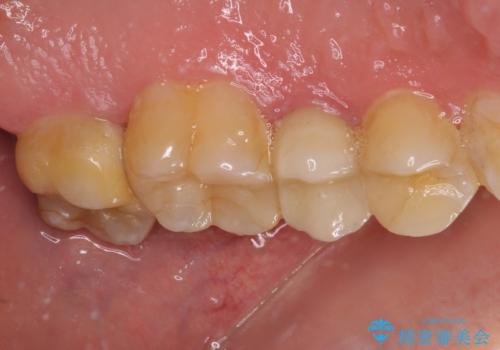

欠損歯質は比較的小さかったため、セラミックインレーにて修復治療を行いました。

来院されたときには、神経を全て取り除くことになるであろうと思っていらっしゃいましたが、結果としては歯根部分の歯髄を残すことができました。

後日状態を確認したところ、残された神経に異常は認められませんでした。